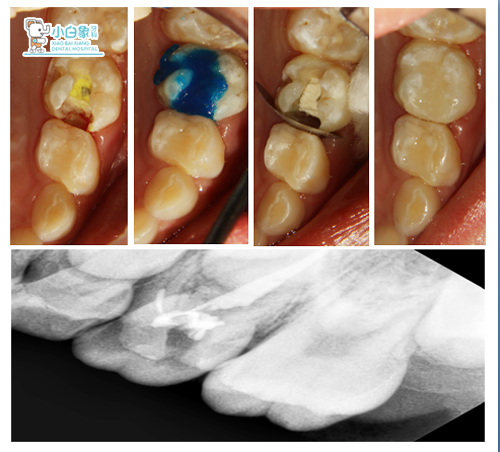

65暂封在,探诊(-),牙龈无红肿。

治疗过程

65去暂封,开髓,揭顶,拔髓,清理根管,生理盐水冲洗,隔湿干燥,根管内置VT,磷酸锌垫底,纳米充填及边缘纳米封闭,调合。